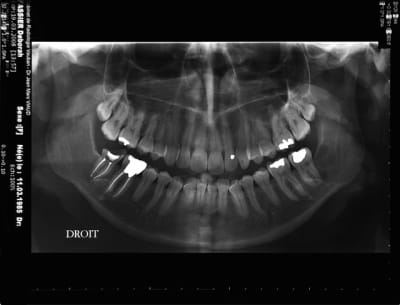

Extraction en 2004

La patiente ne revient pas après, pano demandé par un confrère en 2007 mais la patiente ne retourne pas le voir

Cadeau cette année elle vient pour faire finir 47

Pano demandé

j'ai le scan mais pas ici la corticale linguale est reduite à sa plus simple expression et le kyste remonte sur le trajet du nerf et s'etend aussi en vestibulaire

tu es sur que la 37 n'est pas en cause?

le problème c'est que je n'ai pas revu la patiente pendant 4 ans et que je ne sais pas l'etiologie exacte

je "subis" mon premier problème de dent de sagesse, si j'avais eu à traiter lors du 2° pano ça ne me faisait pas de soucis, mais là!

t'es sûr que la 47 est conservable?

idem pas de suivi depuis 2005, donc je pense qu'elle est HS.

à priori 31/03/2006 pas si vieux que ça je croyais que c'etait 2004, donc évolution rapide

ça peut être également un kyste dentigère laissé en place car il me semble que le kyste est déjà présent sur la première pano et elle est en rapport partiel avec le collet de 38 enclavée mais ça n'est pas caractéristique.